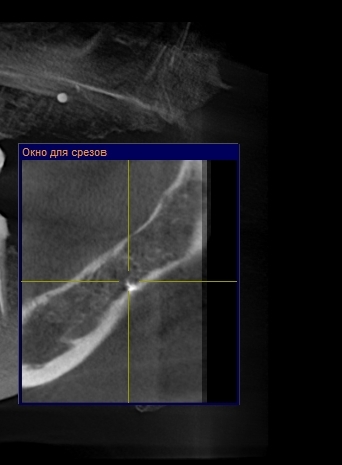

Может ли быть, что через пять лет мне аукнулся неудалённый материал, и боли будут только усугубляться? Прилагаю скриншот КТ

Теоретически ваши симптомы могут быть связаны с инородным материалом в надкостнице, но я не думаю, что причина ваших беспокойств связана именно с этим материалом. Необходимо хорошенько изучить область беспокойства.